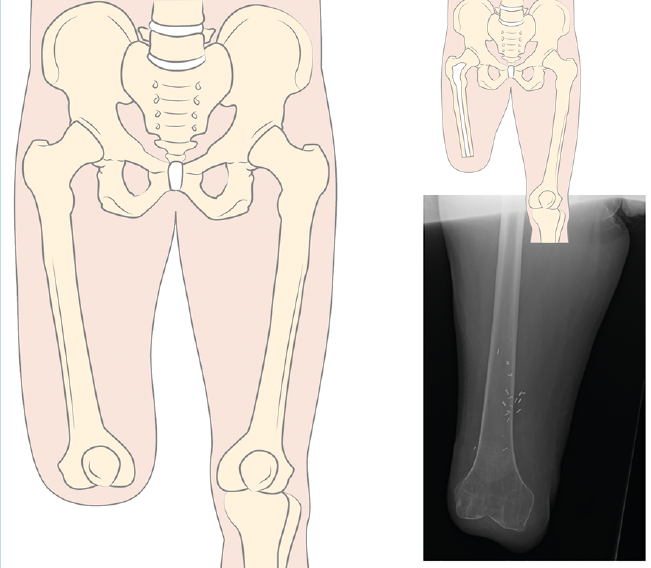

Siempre que la viabilidad de una amputación TT no sea posible, debemos considerar la DR antes que la amputación TF, donde la preservación de los cóndilos femorales facilita la adaptación de un encaje con apoyo distal del muñón (Figura 1). Clínicamente, el apoyo distal es la ventaja más importante en las DR con respecto a la amputación TF, ya que permite transferir directamente la carga distal al muñón femoral y, de este modo, aumentar la independencia en la marcha y reducir el consumo de oxígeno(6,7).

Figura 1. Desarticulación de rodilla.